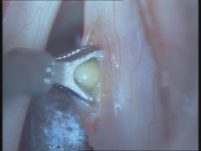

ניתוח ציסטה צעד 3:

ניתוח ציסטה צעד 4: